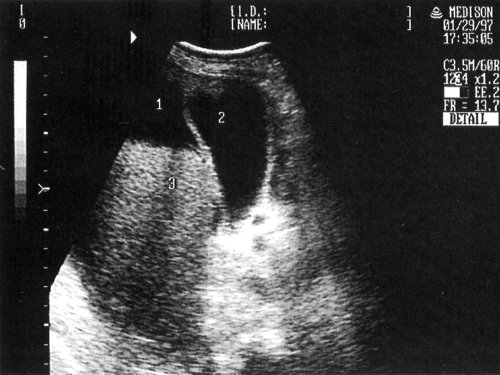

Рис. 7. Эхографическая картина одного из вариантов декомпенсированного цирроза печени: 1 - асцит, 2 - желчный пузырь, 3 - печень.